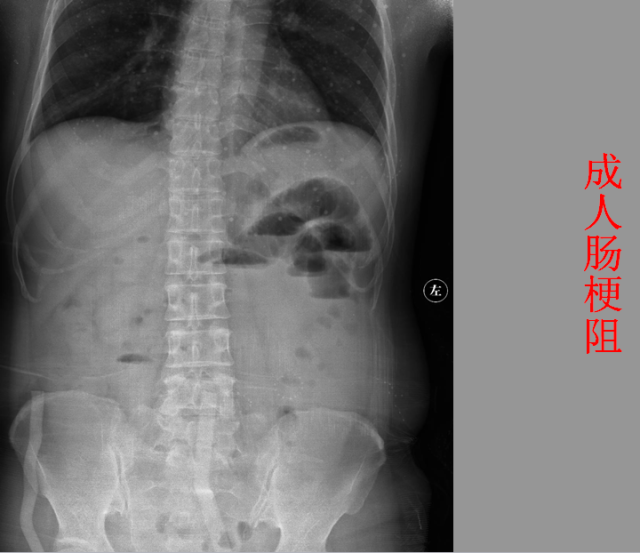

急腹症篇

05